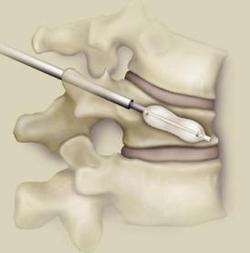

The most common spinal disorders and conditions treated by sbi are cervical and lumbar spinal stenosis and disc herniation.